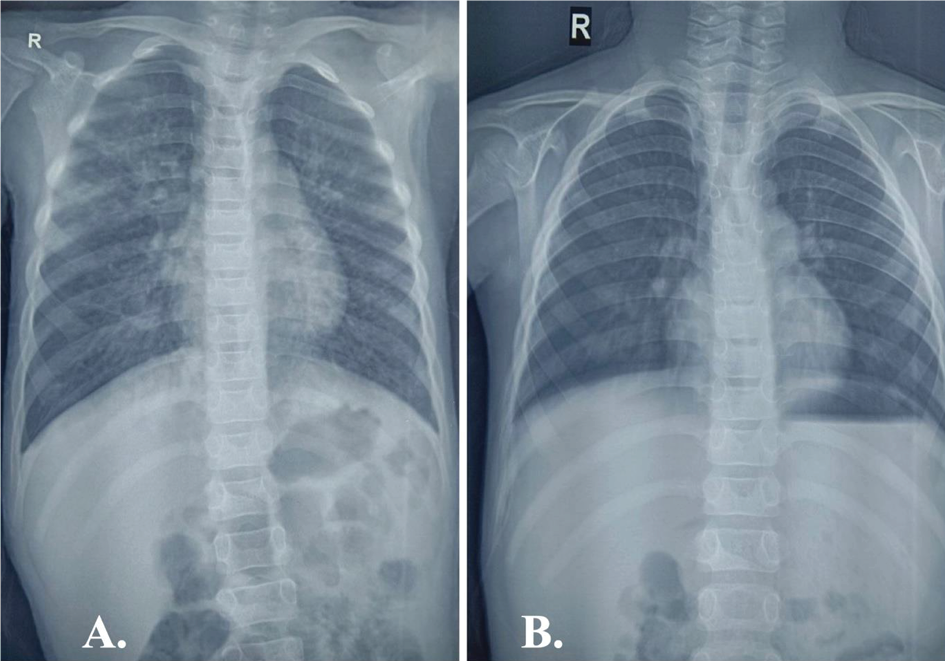

There was also evidence of bilateral conjunctival congestion and chemosis. On auscultation, coarse crepitations were evident predominantly over the right upper lung field. Heterogeneous opacities involving the right upper lung zone were noted in the chest radiograph (Figure 2).